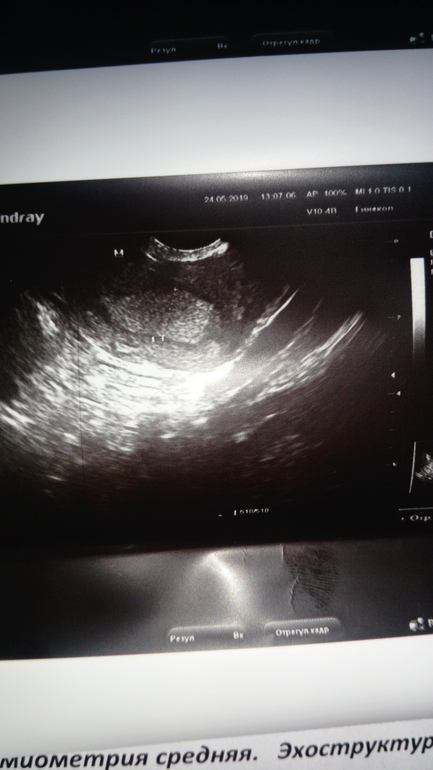

Девочки. 34 день задержки, тесты отрицательные. Была сегодня на УЗИ поставили мультифоликулярные яичники и под вопросом полип, но смутило что узист с начало было кинулся ставить последние месячные, как одумался и говорит д нее это не беременность срок должен быть больше типо это полип скорее всего и надо будет переделать узи после месячных. Не ужели можно спутать полип с беременностью?

Пройдите узи на 7 дц, тогда станет понятно-полип или нет. У меня на 19 дц (из 28) тоже увидели образование, ставили полип под вопросом. Но врач сразу предупредил, что может просто эндометрий так разросся и уйдет во время месячных. Так и получилось. Размер был 1,7 см. Плодное яйцо на узи чуть иначе выглядит, и если бы его у вас увидели, то тест был бы //

Да, можно спутать, и полип и ПЯ на самых ранних сроках выглядят маленькой чёрной точкой. Но, при найденом ПЯ у вас должны уже были полоски на тесте сравняться.